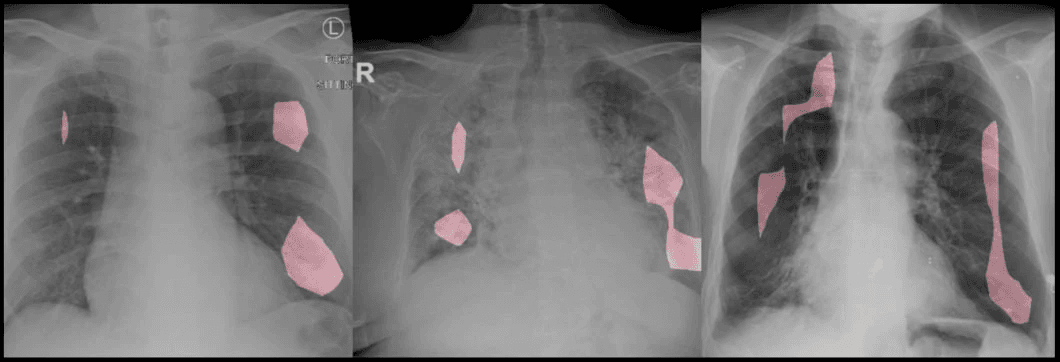

تجزئة الصورة Image Segmentation

تجزئة الصورة تهدف إلى تقسيم الصورة إلى أجزاء مختلفة بناءً على الكائنات الموجودة فيها. هذا يسمح بتحديد كل جزء من الصورة بدقة عالية.

تُستخدم الرؤية الحاسوبية في المجال الطبي لتحليل الصور الطبية مثل الأشعة السينية والتصوير بالرنين المغناطيسي لتحسين التشخيص والعلاج.